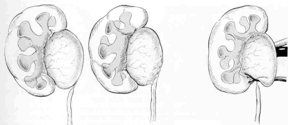

Para se tornar um Cirurgião Pediátrico, o médico precisa fazer dois anos de residência em Cirurgia Geral e mais três anos de residência em Cirurgia Pediátrica, onde verá as diferenças existentes no tratamento dispendidos a um adulto e a uma criança, ganhando habilidade no manuseio desses pacientes tão especiais. Normalmente as cirurgias são mais delicadas, realizadas sob anestesia geral e não necessitam de dormir no hospital (porém muitas delas podem ser realizadas em regime de Hospital Dia com internação que varia de 6 a 12 h). Casos cirúrgicos comuns em crianças são as hérnias inguinal e umbilical, cistos da região do pescoço como os branquiais e o tireoglosso, testículos que não estão situados na bolsa testicular, hipospádia e outras malformações do aparelho urinário, fimose, anquiloglossia (“língua presa”), tumores e doenças gastrointestinais.